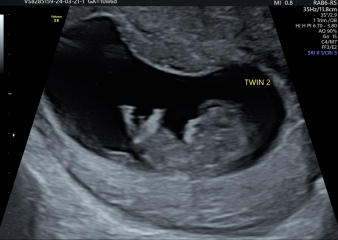

Hi everyone! We had a scan today (delayed our original early scan after we ended up at the EPU a few weeks back) and both twins are doing well and measuring at 10 weeks! It definitely feels more real now they resemble something, and we had a few little arm waves ❤️ very cute seeing them next to each other! Very ready for this nausea and exhaustion to ease up! Hope everyone else who has scans this week goes well.

OCTOBER 2024 BABIES :) THREAD 3

@journeytomum wow look at those lovely twins! Xxxx